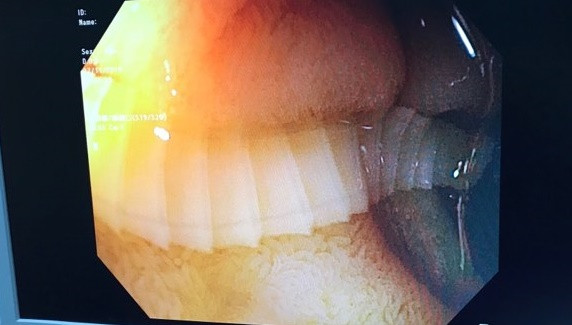

Hình ảnh nội soi con sán dây bò dài 1m sống trong tá tràng bệnh nhân. Ảnh: BVCC

Bác sĩ Tăng Trung Hiếu - Khoa Nội soi (BV Chợ Rẫy), cho biết sán dây bò trưởng thành có thể dài từ 2-4 m, thân có khoảng 800-1.000 đốt sán trắng dẹt.

Sán dây bò thường ký sinh ở ruột non nên hấp thu hết các chất dinh dưỡng, khiến bệnh nhân bị suy dinh dưỡng, rối loạn tiêu hóa, đau bụng, thiếu máu kéo dài. Bác sĩ khuyến cáo người dân nên ăn chín, uống sôi và dùng thực phẩm có nguồn gốc rõ ràng.